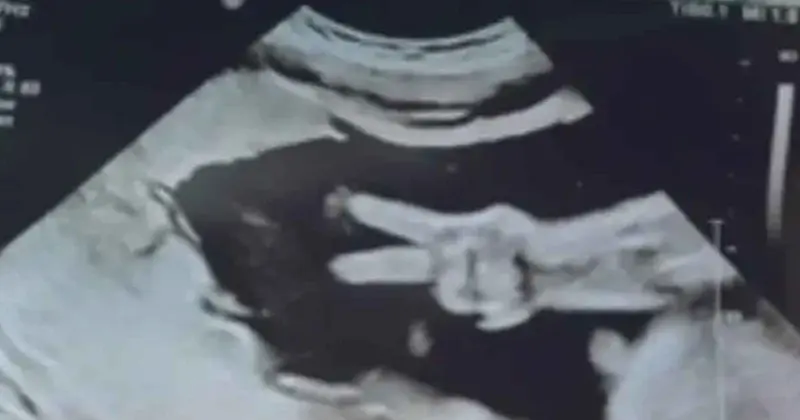

Y es que una pareja en Estados Unidos tuvo un día lleno de amor y ternura luego de que acudieron con el ginecólogo a un estudio de rutina, pero quedaron llenos de asombro cuando su bebé los saludó de una forma muy peculiar, y es que la pequeña hizo la señal de amor y paz.

“El técnico estaba mirando a su alrededor, observando cosas, y de repente estos dos dedos aparecieron”, comentó Kyle Weener, la mamá de la bebé.

Esta linda sorpresa sacó muchas risas a la pareja y al médico, quien no dudo en capturar el momento especial para que los padres de la bebé lo tuvieran con ellos.

La bebé, que tiene 31 semanas, será llamada Eleanor o Eli.